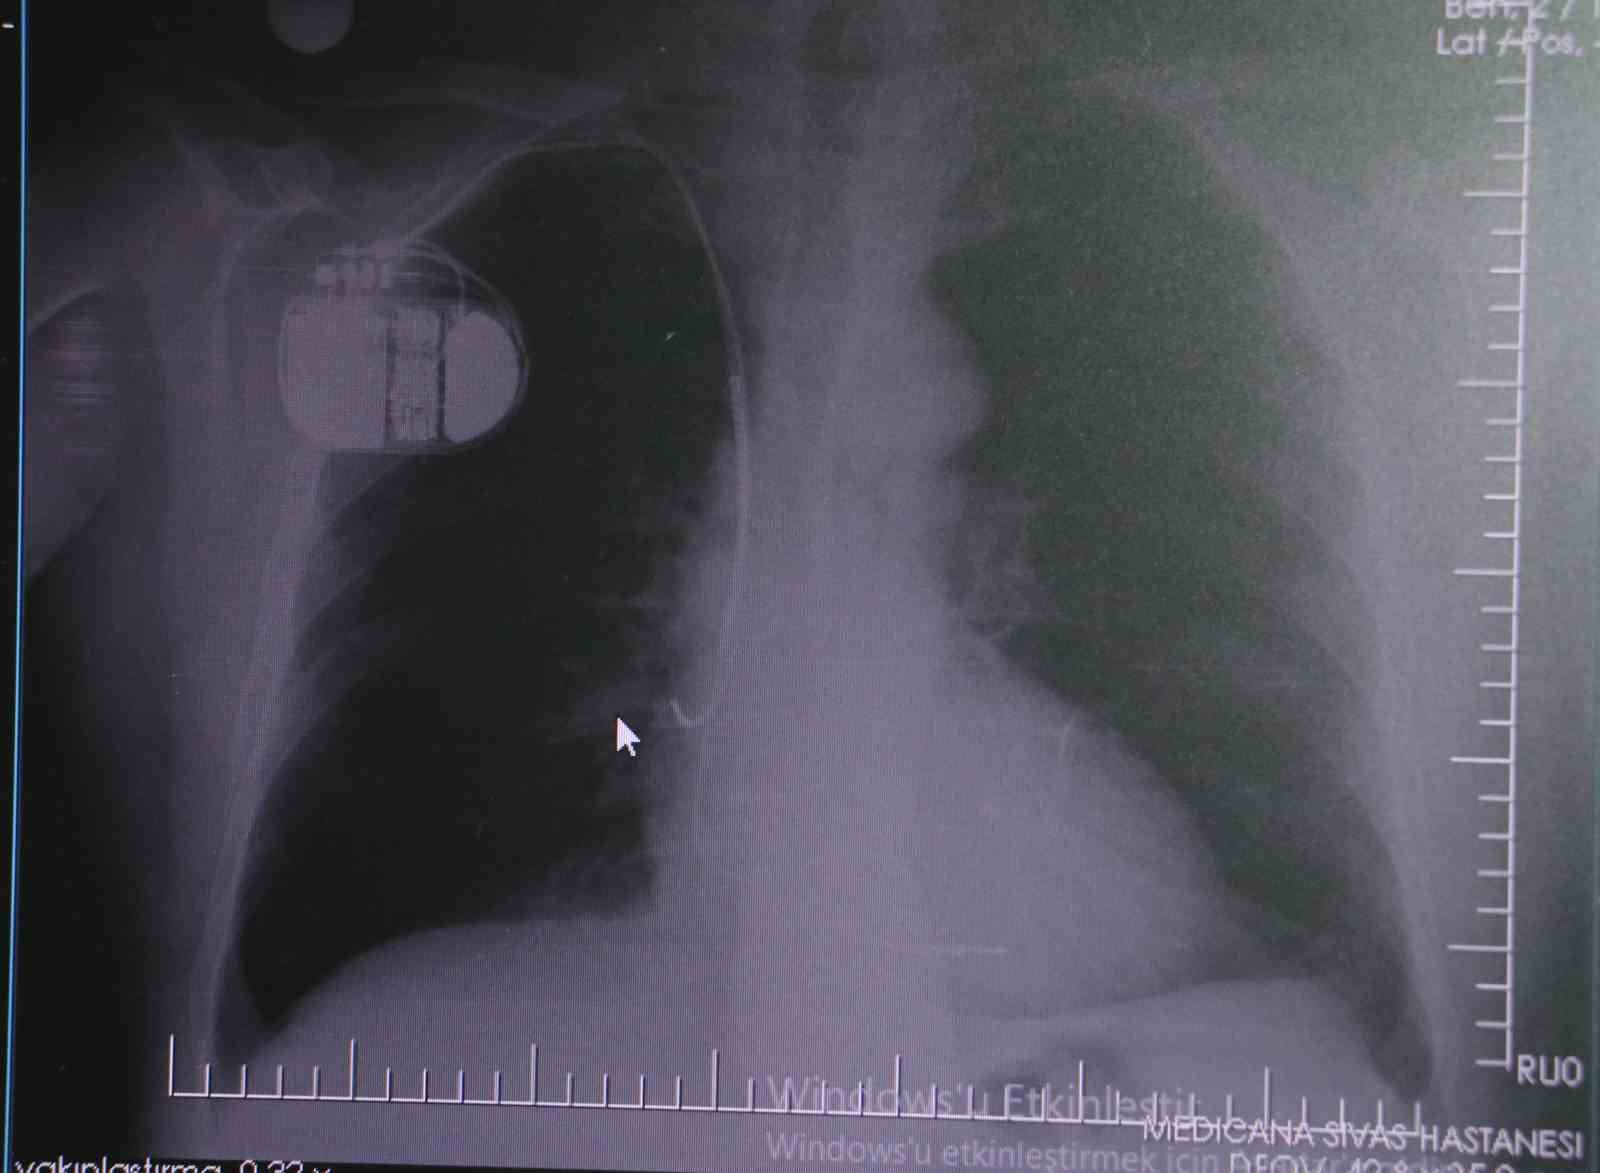

Konuya ilişkin açıklamalarda bulunan Sivas Medicana Hastanesi Kardiyoloji Bölümü Uzmanı Dr. İsmail Erdoğu, kalp pilinin önemine vurgu yaptı. Erdoğu, Yeni nesil kalp pillerinin MR cihazlarına girmeye imkan sağladığı, ancak tarama cihazlarından geçmenin önerilmediğini ifade ederek, "Soğuk hava nedeniyle oluşan titremeler, kalp pilinin kalbin durduğunu sanmasına ve yanlış şoklamaya yol açabilir. Bu nedenle hastalarımızın bu dönemlerde daha dikkatli olmalarını öneriyoruz" dedi.

Kalp pilleri ile MR cihazına girilebileceğini belirten Erdoğu, "Çok büyük bir ameliyat değil ama yine de ciddi bir cerrahi işlem. Kalp pili, tıpta son 30 yılda yaşanan gelişmelerden en büyüğü. Bir bilgisayarın küçültülüp insan vücuduna konulmuş hali aslında. İnsan ömrünü ciddi oranda uzatan bir tedavi. İnsanlar bir şokla hayata tutunurken, pil olmasaydı öleceğini düşündüğümüz birçok hastamız var. Kalp pilinin bu özelliği, uygun hastalarda ciddi oranda ani ölümü engelliyor. Hastanın başına gelecek bir kalp durması durumunda yanında bir sağlıkçı yoksa, onun ritmini düzeltecek defibrilatör cihazı yoksa hastayı hayatta tutmak mümkün değil. Uygun endikasyonlarda kalp pili olduğu zaman, pil hastaların ritmini algılıyor ve acilde yapılan şoklamayı yaparak hastayı hayata döndürüyor. Kalp pillerinde yeni teknolojilerle MR’a girmek mümkün, tomografiye zaten girebiliyorlar. Tarama cihazlarından geçmelerini uygun görmüyoruz. Bu tarz durumlarda hastalarımız ’kalp pilim var’ dediğinde muaf tutuluyorlar. Kalp pilleri ciddi teknolojik cihazlardır. Vücudun içindeki titreşimi, örneğin mikser kullanmak, kolunu sallayacak herhangi bir eylem kalp pilinde olumsuz etki oluşturabilir. Soğuk havalarda vücutta oluşan ciddi titremeler kalp pilinin hafızasını karıştırıp kalbin durduğunu düşündürebilir ve gereksiz şoklama yapabilir. Bu tarz kişilerin soğuk havalarda daha temkinli olması gerekir" diye konuştu.